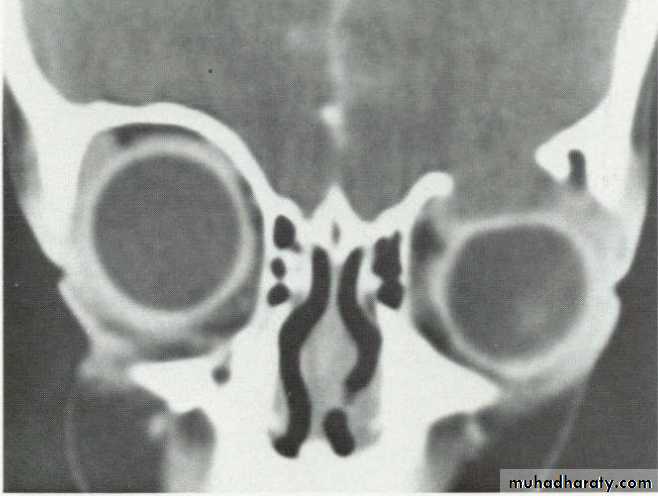

Investigation: CT shows a soft tissue mass with thinning or erosion of the bony walls of the sinus.

Treatment involves complete excision.